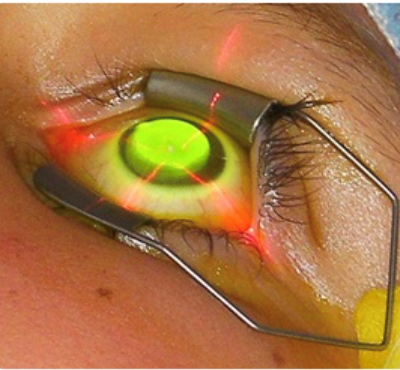

Crosslinking da córnea: o objetivo desse tratamento é fortalecer a estrutura da córnea e impedir a progressão do ceratocone. A técnica consiste na retirada das células superficiais da córnea, aplicação de um colírio à base de riboflavina (vitamina B2) e exposição da córnea a radiação ultra-violeta A (UV-A). Essa reação química causa um aumento da ligações covalentes entre as fibras de colágeno da córnea. Isso resulta no fortalecimento, aumento da rigidez da córnea e estabilização da doença.